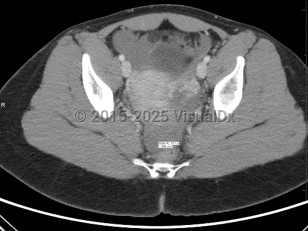

The term ectopic pregnancy refers to implantation of a developing blastocyst at any location outside of the endometrial cavity. Ectopic pregnancies can be found in the cervix, cornua, fallopian tubes, ovaries, or a prior cesarean delivery scar, or, more rarely, attached to the abdominal lining, bowel, or other viscera. The most common location is the fallopian tube, specifically the ampulla, which accounts for about 70%-80% of cases, followed by the isthmus and fimbria. Prevalence is estimated at 25 in 1000 pregnancies, with fewer than 200 000 cases in the United States per year. It is a medical emergency.

Ectopic pregnancies are, by definition, nonviable. If left untreated, they may cause their containing structure (eg, fallopian tube, cornua, scar) to rupture, leading to acute blood loss and subsequent morbidity and possibly death. Black women are nearly 7 times as likely as White women to die from the condition due to health disparities and access to care. Improved technology (biochemical markers, ultrasonography, etc) has enabled health care practitioners to identify a majority of ectopic pregnancies before rupture to reduce associated morbidity and mortality.

Presentation can vary. Patients may present with a positive home pregnancy test and unilateral lower quadrant pain that is often sharp / stabbing in nature. Some will present after tubal rupture and be hemodynamically unstable. Others may present with only vaginal spotting and be unaware they are even pregnant. Therefore, one must have a high index of suspicion when a patient arrives with a positive pregnancy test and symptomatology. As many as 18% of women presenting to the emergency department with first-trimester bleeding, pain, or both will be found to have an ectopic pregnancy.